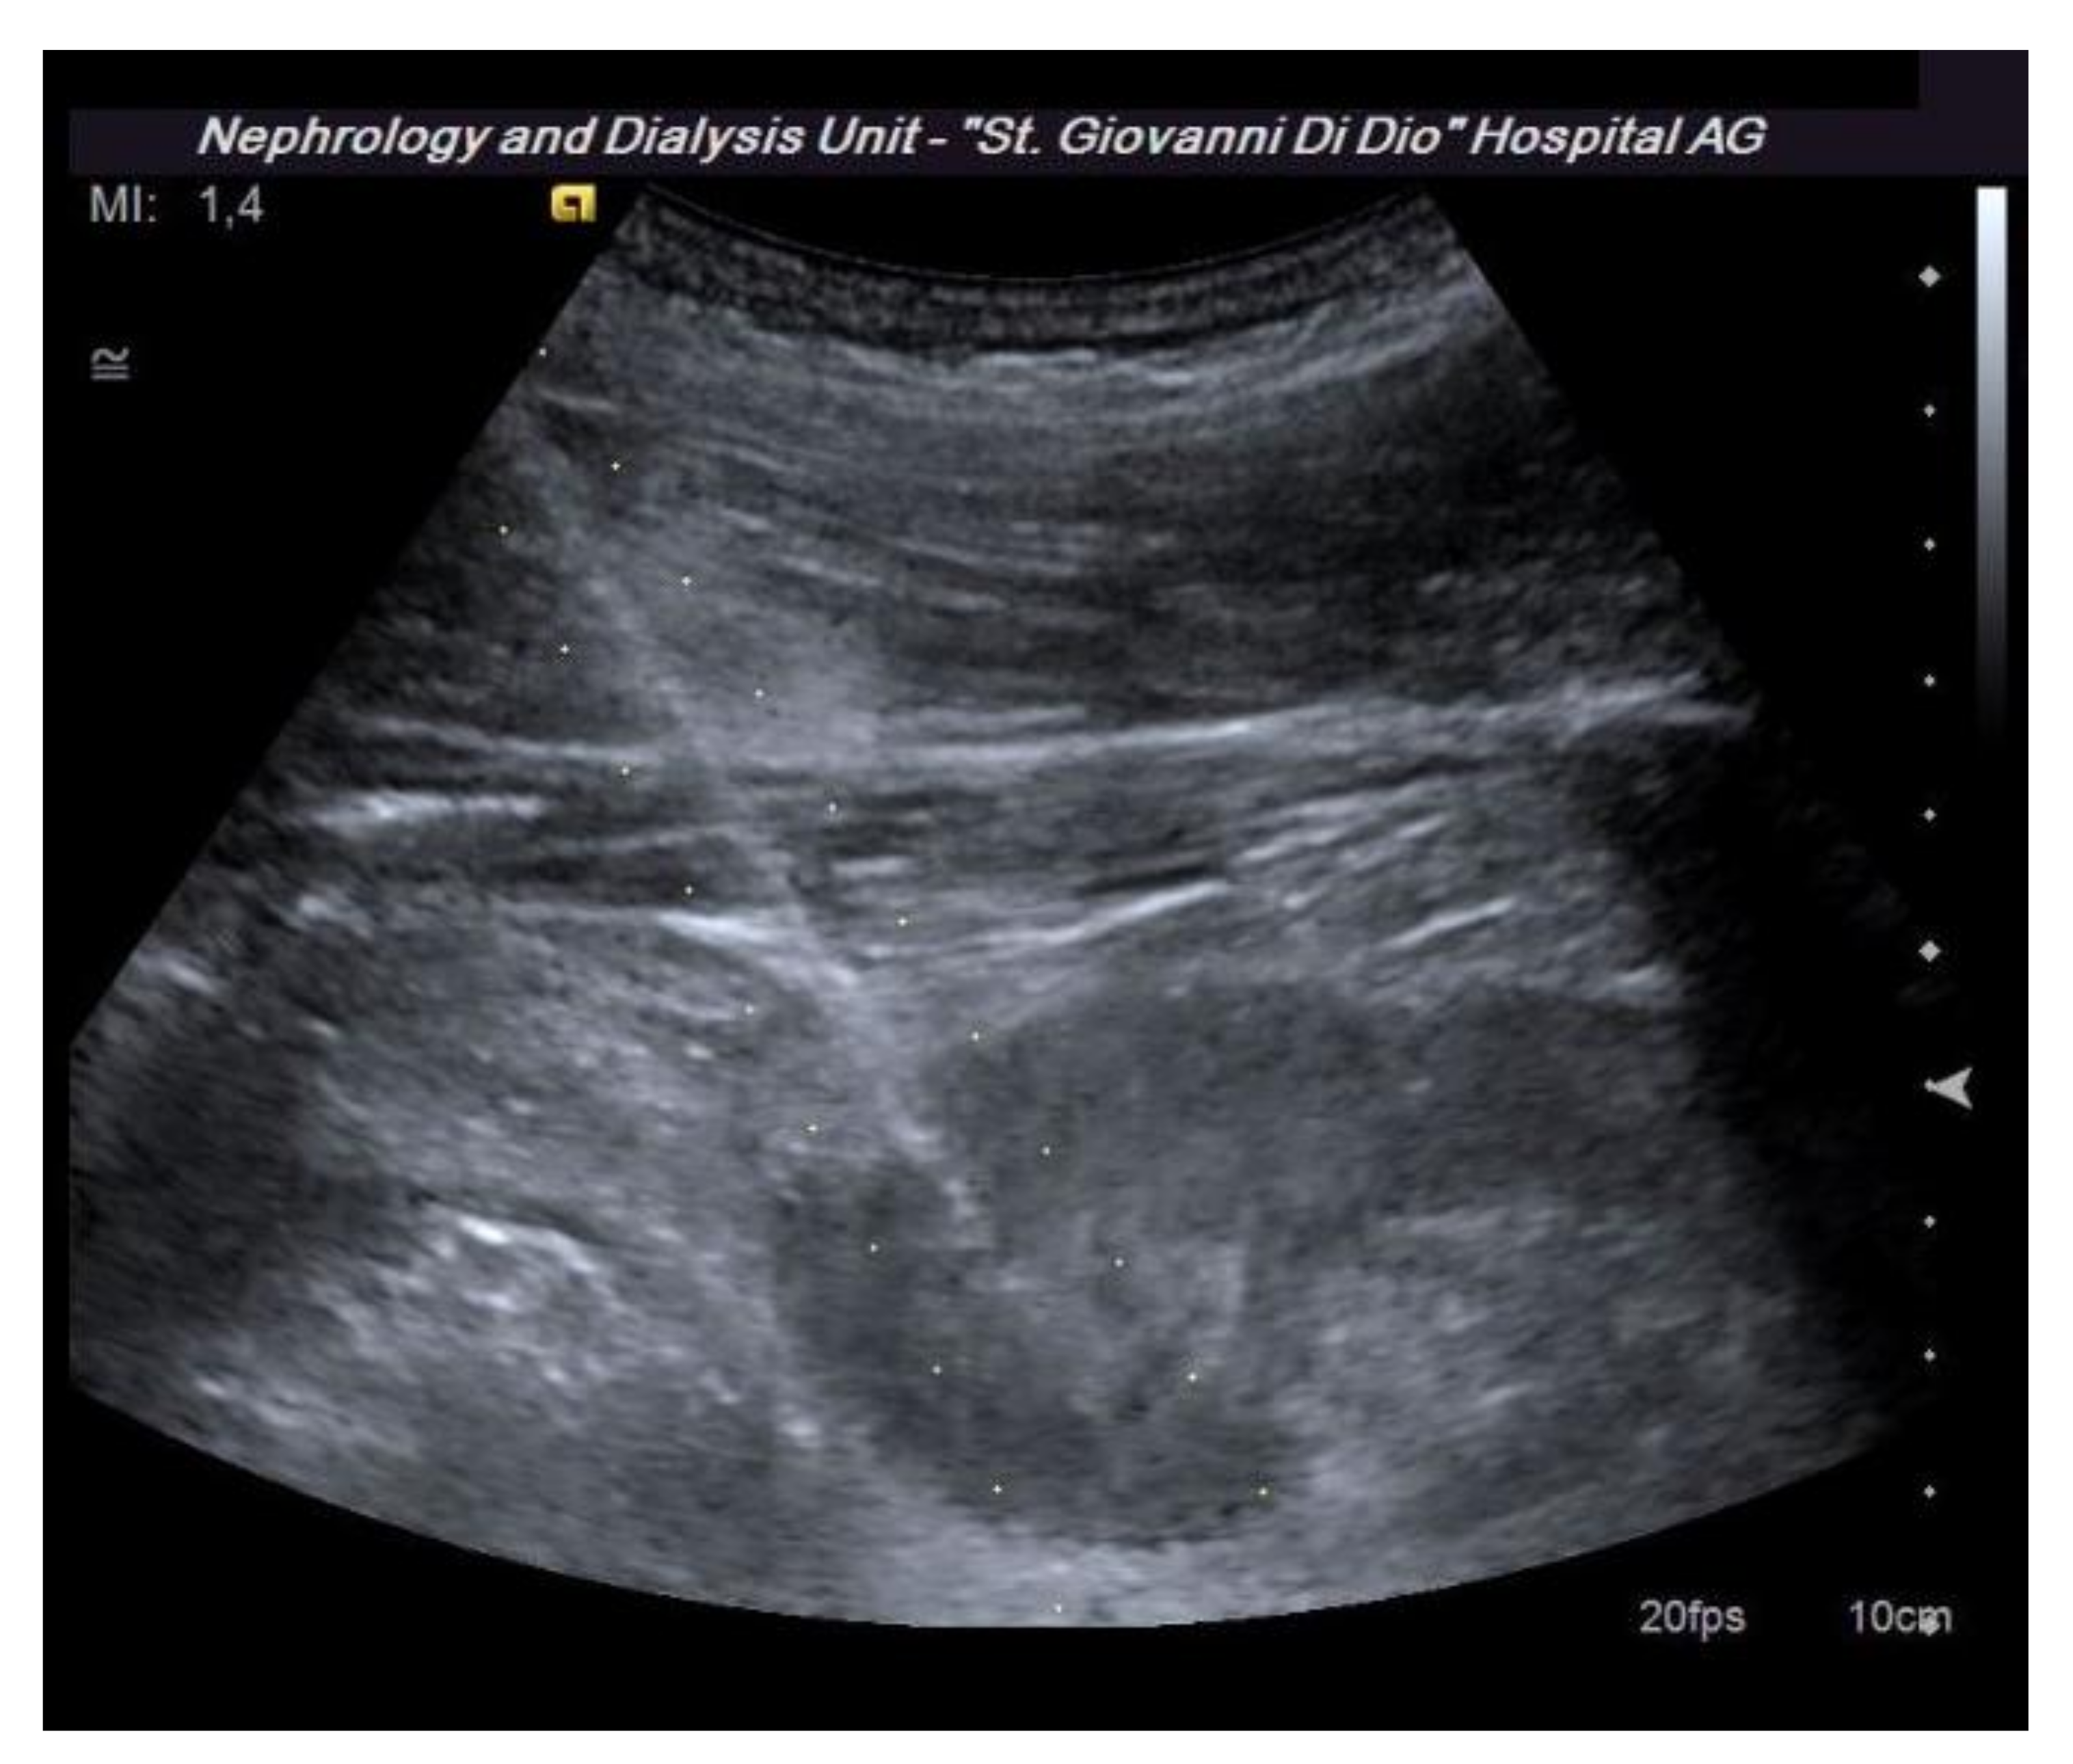

7. Position of the Patient

8. Prebiopsy Ultrasound Study